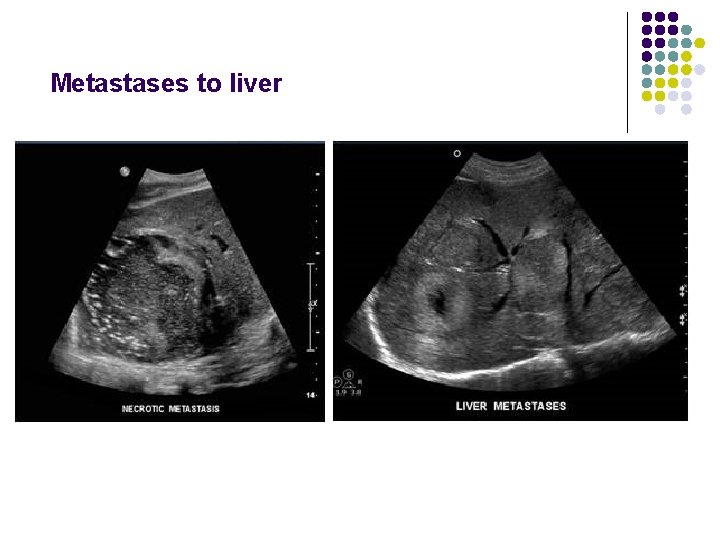

Metastases to liver l l l Organ of origin: colon(42%); stomach(23%); pancreas(21%); breast(14%); lung(13%) Number : multiple(98%); solitary(2%) “Bullseye”:An echogenic center with a surrounding echopenic area Echopenic : Less echogenic than the surrounding liver Echogenic More echogenic than the surrounding liver

Metastases to liver

Metastases to liver